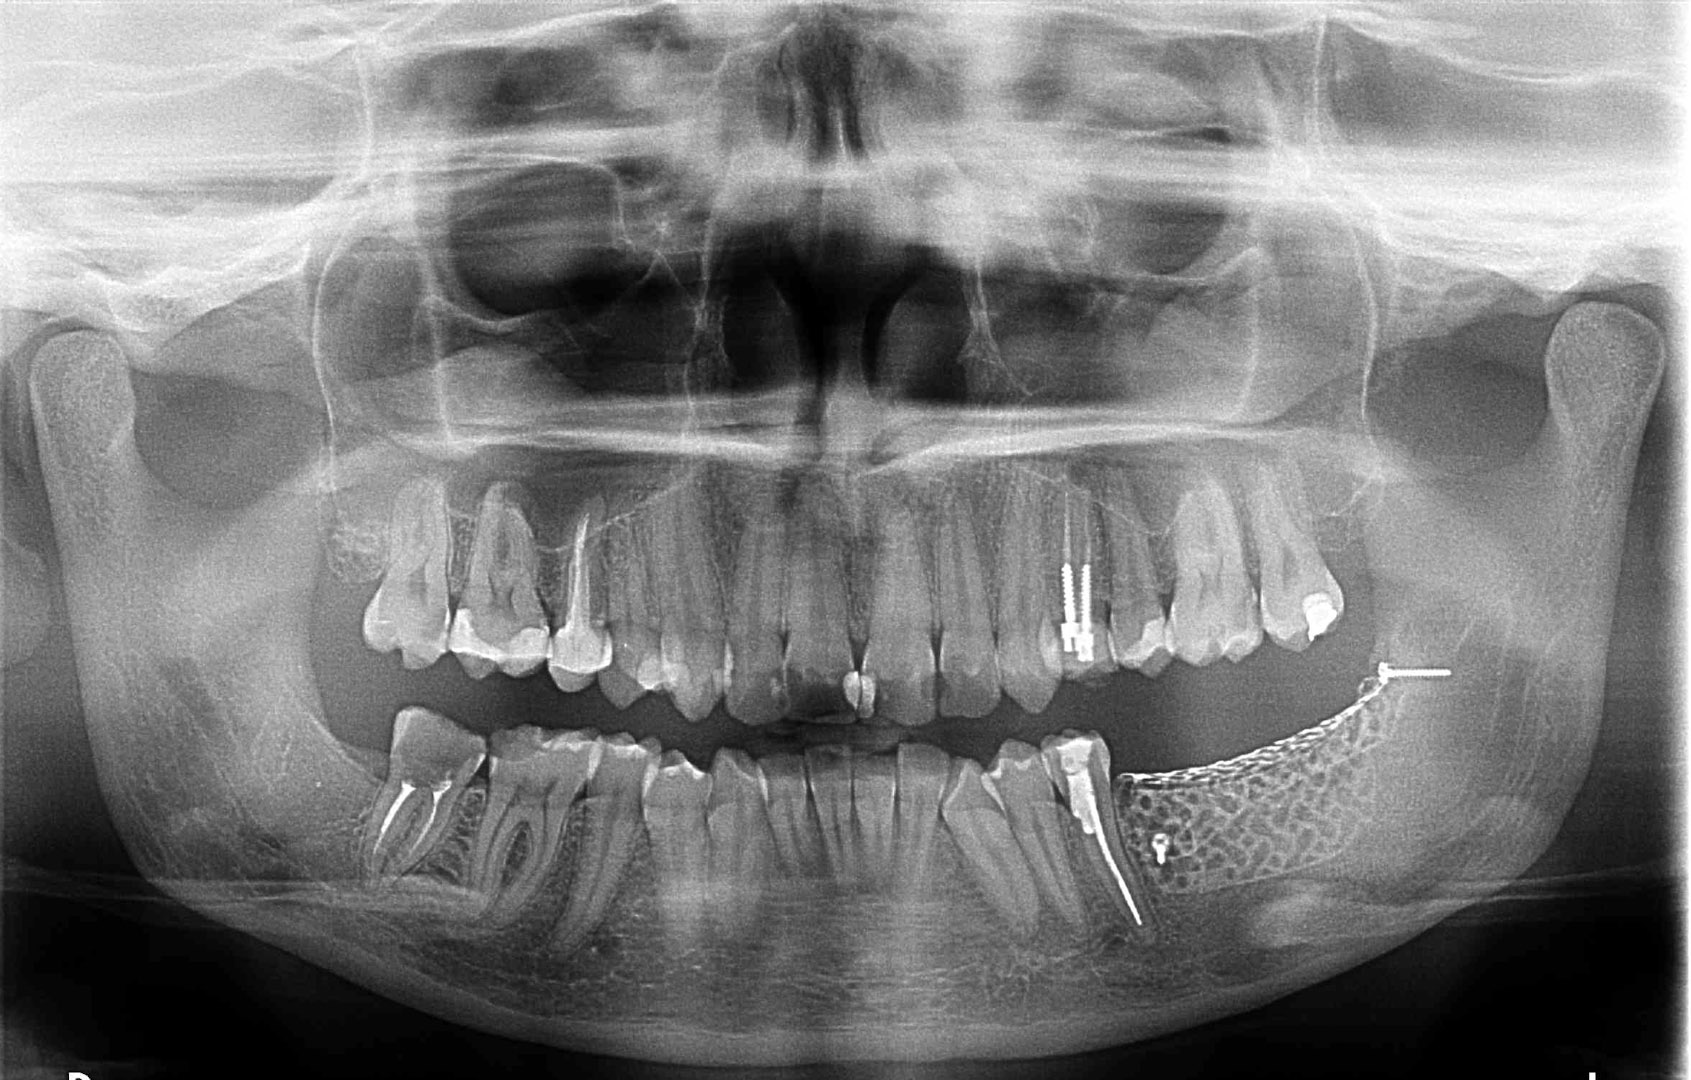

Przed podjęciem leczenia należy określić stopień zaniku kości szczęk oraz żuchwy. W tym celu przeprowadza się badanie kliniczne oraz odpowiednią diagnostykę obrazową pacjenta. Uwzględnia ona zdjęcie panoramiczne OPG jako podstawę dwuwymiarowego obrazowania podłoża kostnego oraz możliwe jest badanie tomograficzne CT lub bardziej precyzyjna tomografia stożkowa CBCT. Opcjonalnie wykorzystywana diagnostycznie tomografia pozwala na bardziej wnikliwą ocenę stopnia zaniku kości w trójwymiarowym, przestrzennym obrazie.

To kolejna metoda umożliwiająca precyzyjną odbudowę zadanego kształtu tkanki kostnej przy użyciu standardowych materiałów kościotwórczych, kości własnej lub PRF oraz zewnętrznego rusztowania w postaci siatki z biozgodnego stopu tytanu. Siatka jest indywidualnie projektowana w technologii CAD CAM i następnie drukowana dla konkretnego przypadku.

Dotychczas stosowane stabilizatory zewnętrzne w formie siatek tytanowych używane do regeneracji kostnej lub w zabiegach odtwórczych w chirurgii szczękowo-twarzowej uwzględniały materiały ręcznie doginane i formowane podczas zabiegu operacyjnego. Zastosowanie technologii CAD CAM dla potrzeb druku materiałów przeznaczonych do indywidualnej rekonstrukcji kostnej znacznie poprawiło precyzję i jakość uzyskiwanych efektów. Wdrożenie biozgodnych stopów tytanu do druku siatek zdecydowanie ograniczyło odsetek powikłań zapalnych.

Siatki stanowią stabilną obudowę – ograniczenie nadające kształt regenerowanej kości przy użyciu upakowanego pod nią materiału. Utrzymują i stabilizują rozdrobniony granulat kościotwórczy, co jest warunkiem prawidłowego procesu gojenia, jednocześnie nadając anatomiczny kształt i zakres odbudowie kostnej sprzed jej zaniku.

Precyzja projektu druku siatki bazuje na dokładności odwzorowania kształtu kości w stożkowej tomografii komputerowej CBCT, co zapewnia ich dobre przyleganie do podłoża kostnego oraz ogranicza powstawanie powikłań w postaci obnażania się siatek.

Metoda rekonstrukcji kostnej w oparciu o indywidualnie drukowane siatki z tytanu dla implantacji wszczepów śródkostnych stosowana jest najczęściej jako dwuetapowa. W pierwszym etapie odbudowywana jest kość, natomiast implanty wszczepiane są po okresie 4–6 miesięcy. Na wgojenie implantów oczekujemy od 4 do 6 miesięcy w zależności od miejsca ich lokalizacji. Siatka tytanowa po spełnieniu swojej funkcji rusztowania dla odbudowującej się kości jest następnie usuwana w dniu wszczepienia implantu. Jeżeli kość spełnia odpowiednie warunki, istnieje możliwość zastosowania modyfikacji siatki tytanowej, która umożliwia jednoczesne wprowadzenie implantów wraz z odbudową kostną. Wariant ten skraca czas od pierwszego zabiegu do wykonania gotowych koron protetycznych na wprowadzonych implantach.